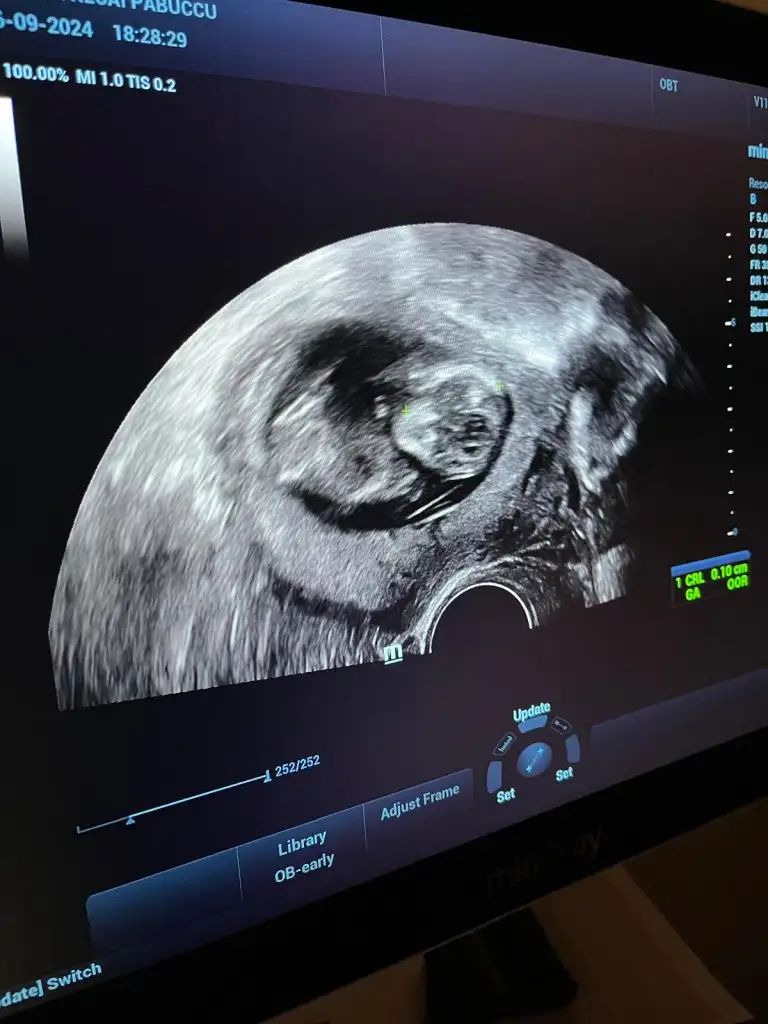

Kimse yok mu12 haftalik karindan ultrason rica etsem cinsiyet tahmini yapabilir misiniz

Başka foto yok mi12 haftalik karindan ultrason rica etsem cinsiyet tahmini yapabilir misiniz

Benimkine de baksanız ilk ve çok merak ediyorumBaşka foto yok mi

Bacak arası fotosu bu doktor kız diyor ama ben hala erkek hissediyorummmCanım hiç belli olmuyor bacak kısımları anlayamayuz böyle

Evet doktor kız dedi ama ben ısrarla erkek hissediyorummm 14. Haftada söylediBence kız bir an öyle hissettim nedenini bilmeden ama tabi ne olursa olsun sağlıklı olsun

Evet doktor kız dedi ama ben ısrarla erkek hissediyorummm 14. Haftada söyledi

Bacak arasını boş gördüğü için demiştir kızda yanılma payı var detaylı ultrasona girene kadar bende erkek hissediyorum ama daha belli değil 15 hafta 2 günlük benim bebişim deEvet doktor kız dedi ama ben ısrarla erkek hissediyorummm 14. Haftada söyledi